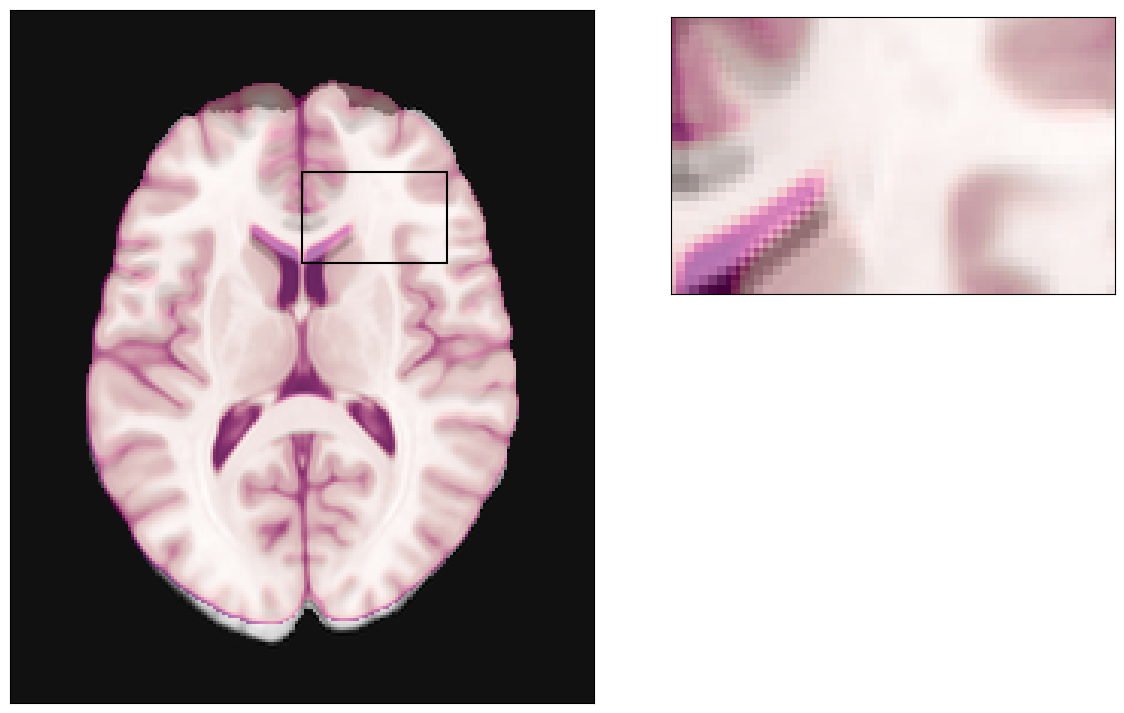

The effects of this physical phenomenon

Then the MRI device will execute the EPI scanning scheme, and sample at the locations given above. The result can be seen in the image below:

For reference, we can plot our MRI (grayscale colormap) fused with the original (ground-truth) anatomy.